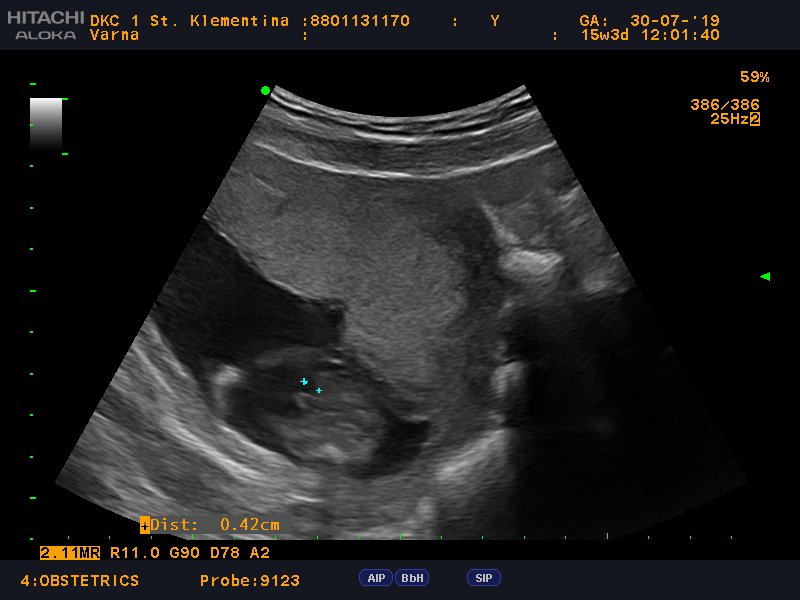

В коя седмица видяхте ембриона и в коя чухме сърдечния ритъм?